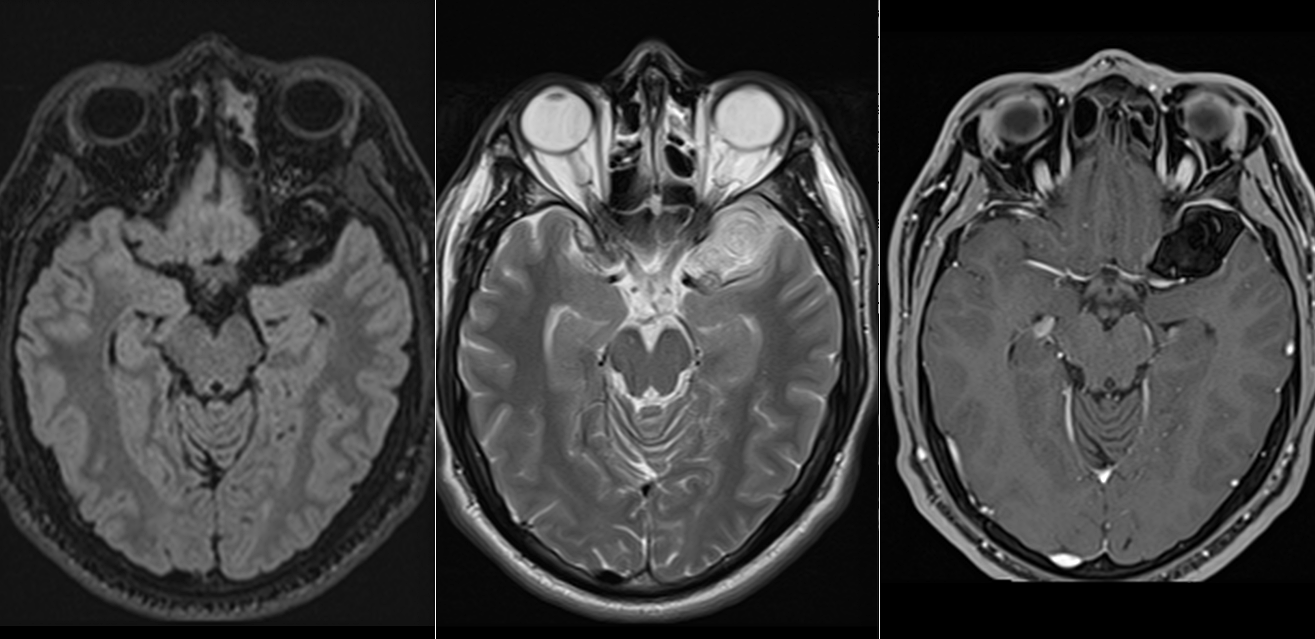

Imagistica prin rezonanță magnetică (IRM):

- Investigația de elecție.

- Chisturile epidermoide:

- Hiposemnal T1, hipersemnal T2.

- Nu se încarcă cu substanță de contrast.

- Apare restricție de difuzie pe secvențele DWI – caracteristică importantă.

- Chisturile dermoide:

- Hipersemnal pe T1 (datorită conținutului lipidic).

- Semnal mixt pe T2.

- Poate avea semnal susceptibil pe secvențe GRE dacă există componente calcificate.

- Poate fi evidentă o fistulă cu exteriorul.